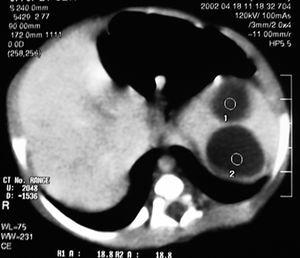

Recién nacido de sexo masculino, segundo hijo de padres jóvenes, saludables. Detectadas por ecografía fetal a las 34 semanas de gestación dos formaciones hipoecogénicas con 23 y 18 mm de diámetro en el hipocondrio izquierdo. Parto por cesárea a las 37 semanas. Test de Apgar 8/10 al primer y al quinto minutos de vida, respectivamente. Exploración física normal. Se efectuó ecografía abdominal en el cuarto día de vida, visualizándose dos formaciones quísticas en el bazo, con 24 y 19 mm de diámetro. Sin otras alteraciones intraabdominales (fig. 1). En el octavo día de vida se efectuó tomografía computarizada (TC) abdominal en la que se confirman las lesiones nodulares intraesplénicas de 23 y 27 mm (fig. 2). Período neonatal normal. Fue seguido en la consulta donde se verificó una disminución progresiva hasta su total regresión a los 5 meses de vida. Estuvo todo el tiempo asintomático y con exploración física normal.

Figura 2. TC abdominal: lesiones nodulares intraesplénicas de 23 y 27 mm.